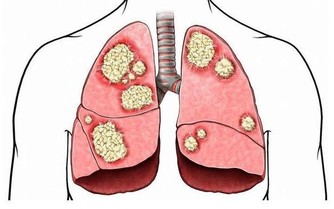

4.氯對人體有什麽危害?

答:氯氣對人體有嚴重危害,它能刺激眼、鼻、喉以及上呼吸道等。引起急性肺水腫及肺炎,濃度高時可麻痹呼吸中樞、出現「閃擊性死亡」。長期吸入低濃度的氯會引起慢性中毒,導致體內產生大量的自由基,加速人體衰老速度。主要病癥為鼻炎、慢性支氣管炎、肺氣腫、肝硬化、動脈粥樣硬化,甚至是癌癥。

10.長期飲用含餘氯的水會導致什麽疾病?

答:心臟疾病、冠狀動脈粥樣硬化、貧血癥、膀胱癌、肝癌、直腸癌、高血壓和過敏等癥狀。

13.餘氯對老人有什麽危害?

答:可導致動脈粥樣硬化、心力衰竭、動脈硬化、心臟病、膀胱癌、肝癌、直腸癌、高血壓。